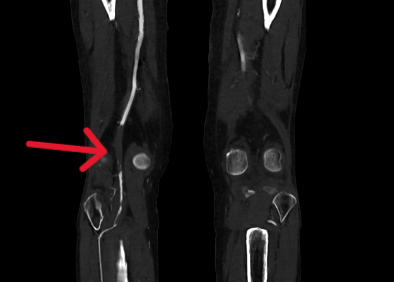

另一个病例中,患者病情更为复杂。术前CTA检查显示,其股浅动脉至腘动脉全程闭塞,血管外科将这种情形称为“长段无光区”。传统治疗中,开通此类如同“水泥管”般的长段闭塞血管,难度极大,术者如同在黑暗中摸索,导丝极易误入内膜下形成夹层,导致手术失败。

2.png

术中,血管外科团队以IVUS为“导航”,在其实时监视下,导丝精准找到血管真腔入口,顺利通过全程闭塞段,成功避免夹层发生,顺利打通患者腿部“生命通道”。针对血管开通后管腔内的严重增生性病变,团队采用准分子激光消融术进行减容处理,通过激光导管冷光源精准气化斑块,进一步恢复了血管正常内径。

经“精准诊断+精准操作”的一体化治疗,手术取得圆满成功。患者术前因严重缺血无法测出踝肱指数(ABI),术后ABI值恢复至0.92并接近正常水平,同时静息痛完全消失,重新恢复了自主行走能力,生活质量得到根本性改善。